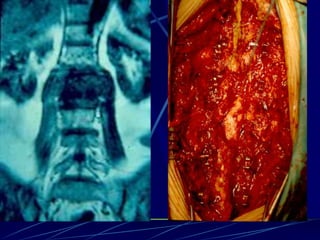

Φυματίωση της σπονδυλικής στήλης